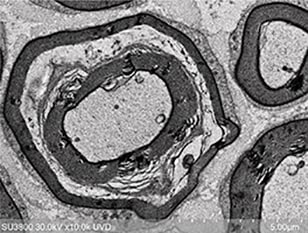

■STEM 홀더(옵션)

-

투과 전자 이미지를 관찰할 수 있습니다.

신규 개발 STEM 홀더와 고감도 저진공 2차 전자 검출기(UVD)를

함께 사용하면 투과 전자 이미지를 손쉽게 얻을 수 있습니다.

박막 시료 및 생체 샘플 관찰에 유용합니다.

가속 전압: 30kV

관찰 신호: STEM 이미지

배율: x30,000

배율: x10,000